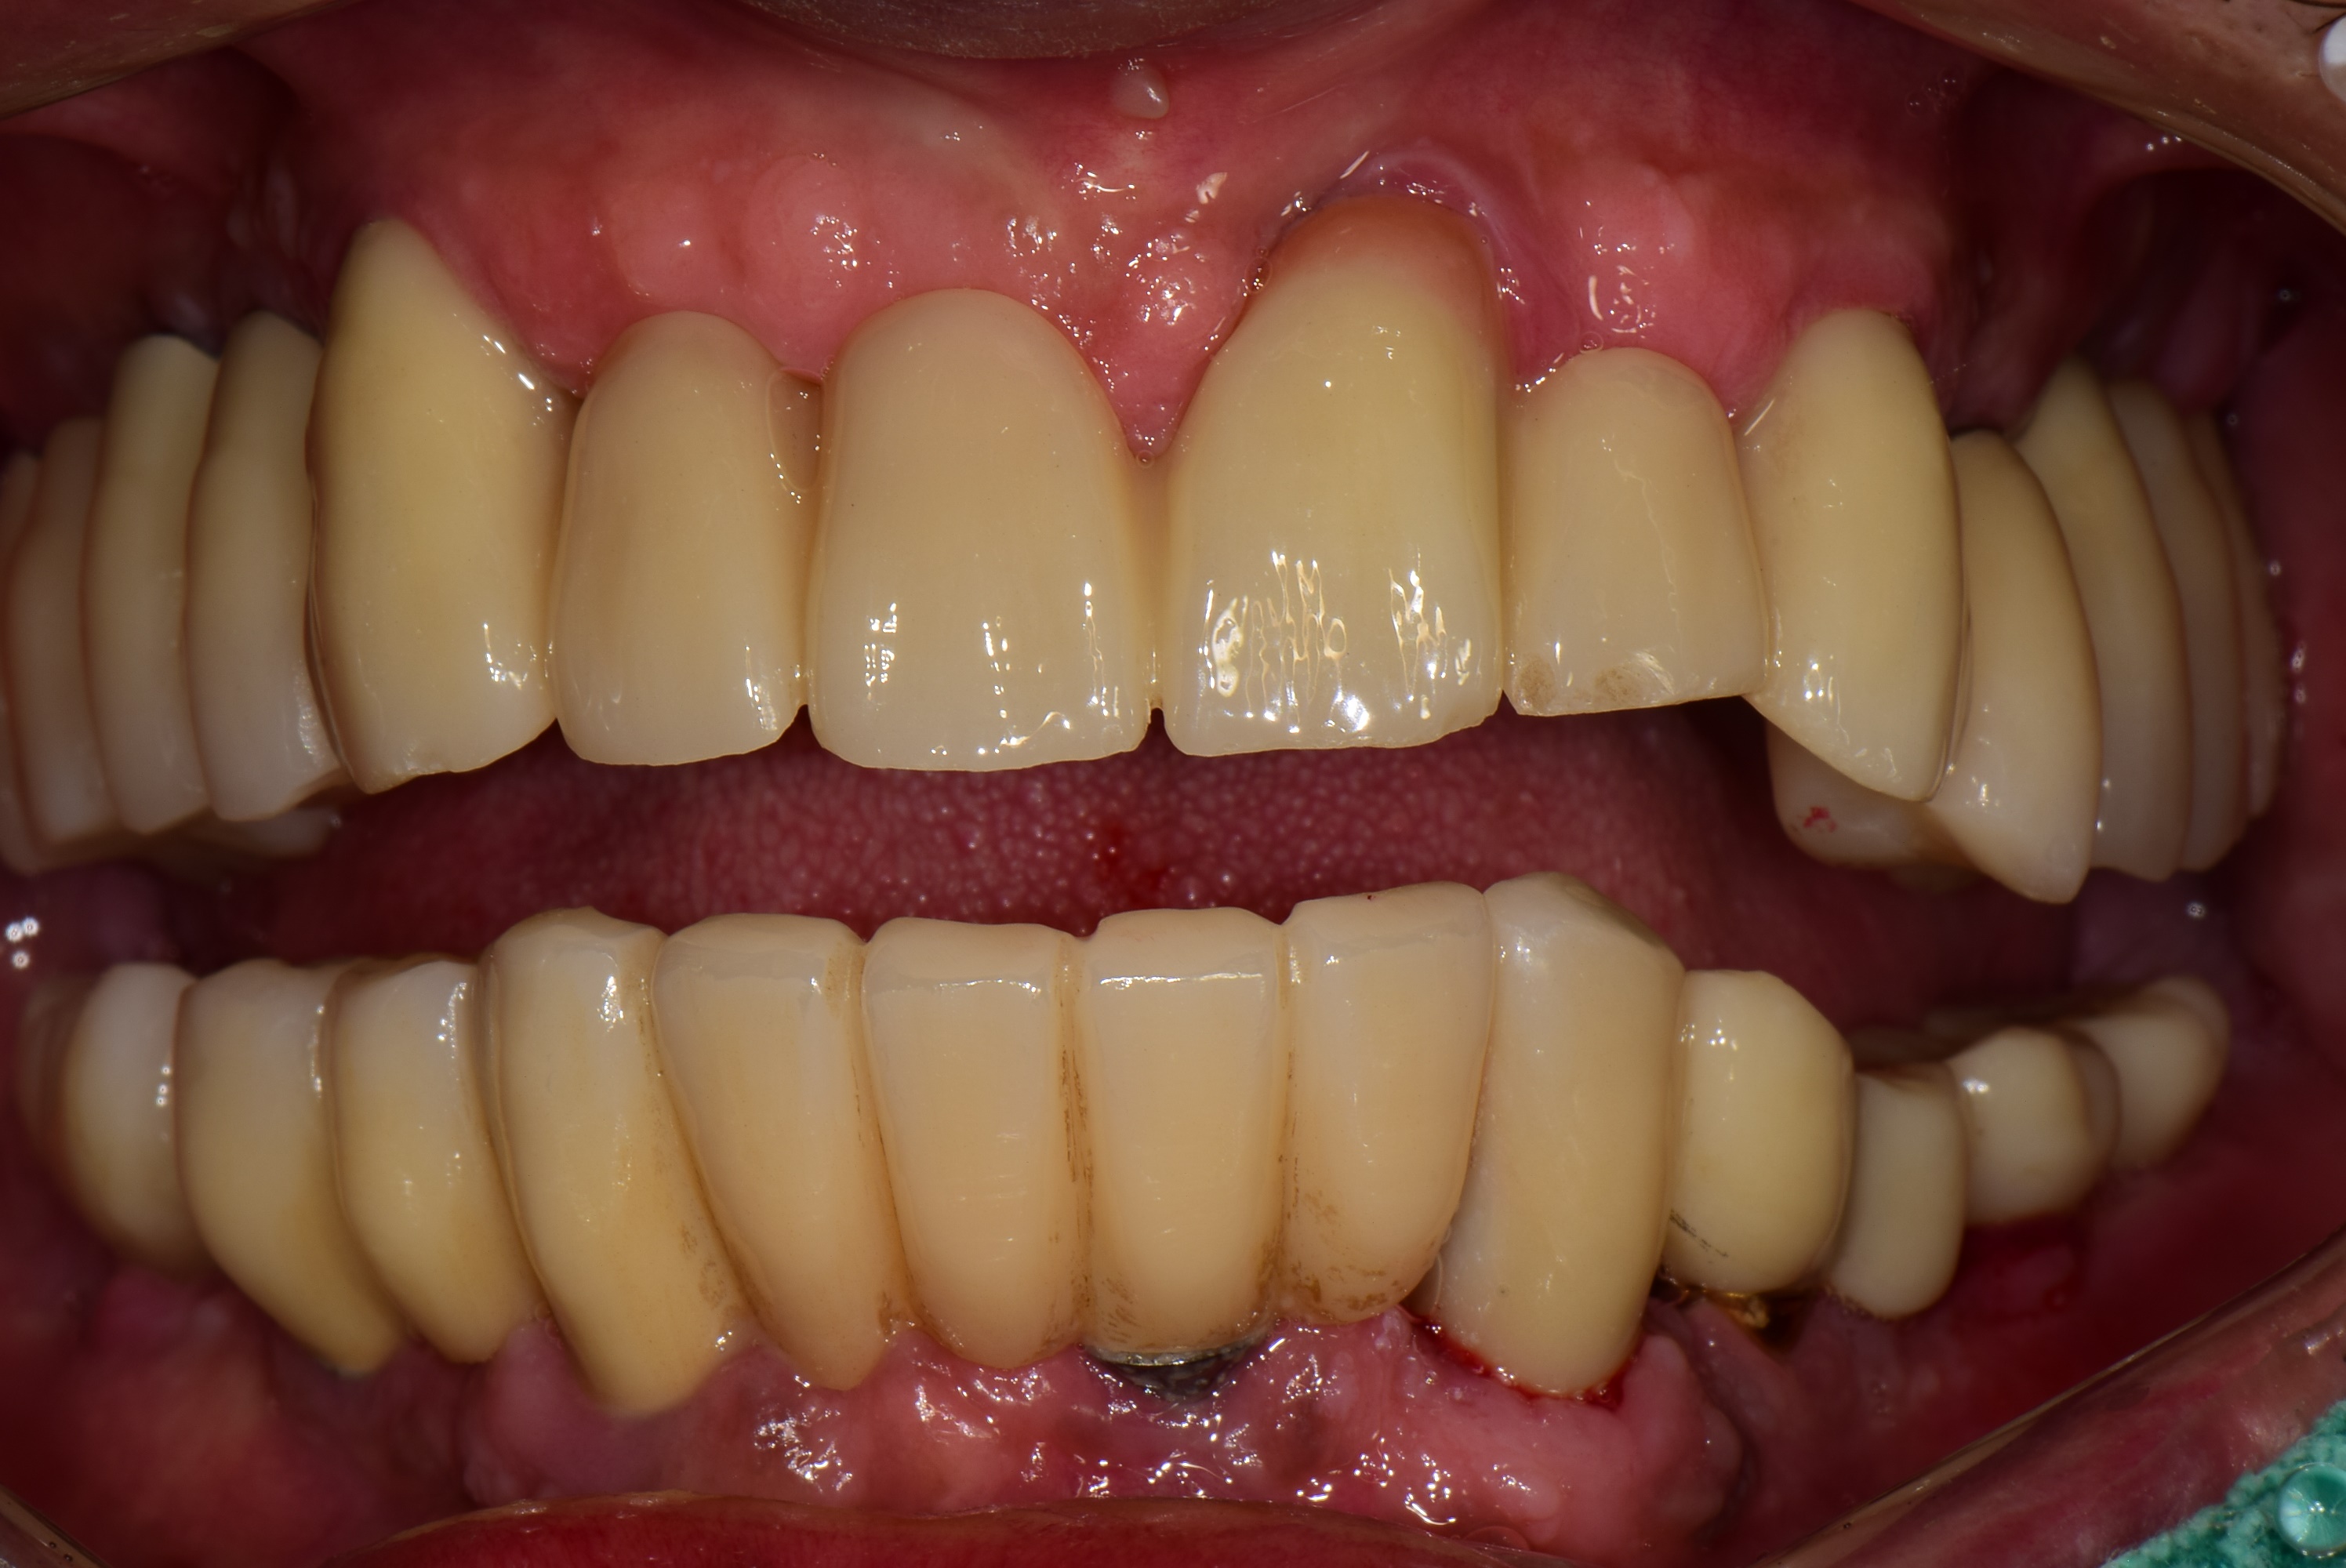

김포 풍무동 서울케이치과 위턱 전체 임플란트 사례

9개 임플란트 식립 후 고정식 보철로 위턱 전체 치아 수복한 사례입니다.

(아래턱 임플란트는 수년 전 타치과에서 식립했으나, 임플란트 주변 치조골이 소실되고 있어 추후 재식립이 필요합니다.)

<치료 후>